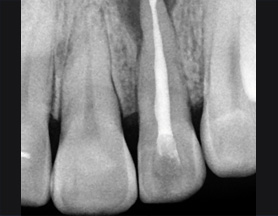

치아 뿌리 주변 염증과 치조골이 녹아내려 통증과 더불어 치아가 흔들리는 상태로 내원한 환자입니다. 우선 큐렛으로 잇몸 속 치석을 제거하였습니다.

뿌리 주변 염증은 신경관을 소독하고 약재를 삽입하는 신경치료를 시행하였습니다.

치근단 염증

신경관 소독

신경관 약재 삽입

약재 주입 후 반응